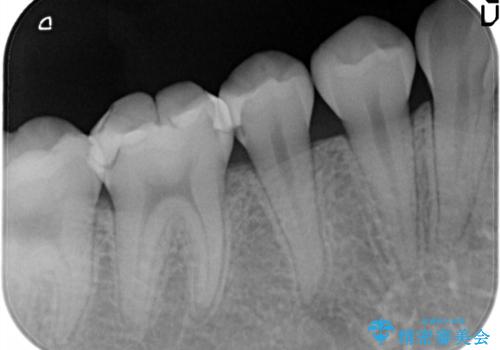

- むし歯の治療を希望されて来院された患者様です。

セラミックインレーによる修復を行っております。

保険治療で使える材料には制限があり、見た目だけでなく精度でも劣ります。当院でのセラミックインレーは歯とのつなぎ目を拡大鏡で確認して精度高く仕上げるため、むし歯のリスクを限りなく少なくできるよう治療します。